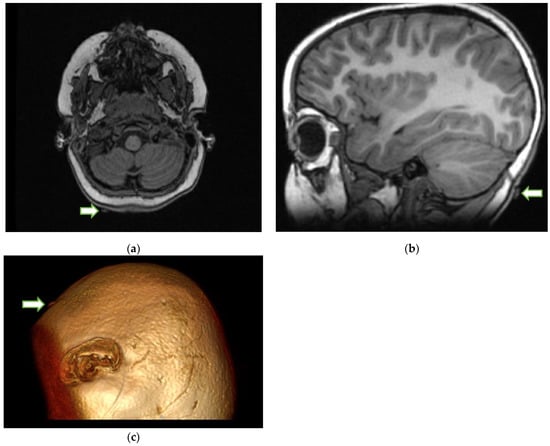

Upon review of the patient’s head imaging, it was determined that the tick could be seen on the MRI (Figure 2) of the brain performed earlier.

The search for a tick on the scalp should be performed on a patient with paralysis. An MRI or CT scan is usually performed for patients with weakness or paralysis. Typically, MRI and CT scans of the head are normal in the context of TP. A normal MRI of the brain in a patient with paralysis should prompt a search, especially in the occipital soft tissues, to identify a tick-shaped extraneous structure on the axial images of the brain. The search for a tick on the scalp can be a daunting task. Locating it on MR or CT may act as a guide to narrow the search area. Sometimes, the answer lies in the most minor of observations. Because the removal of the tick is the main treatment for TP, MRI identification and localization, especially with 3D reconstruction, may play a critical role in these patients, as the tick can be removed before the progressive paralysis causes respiratory failure or even death in rare cases. As TP is frequently misdiagnosed as GBS and other acute ascending motor neuropathies, early tick identification may also prevent further unnecessary diagnostic tests or treatments [1,2,7,8].

Figure 2. Axial T1-weighted (a) MRI of the brain at the level of the medulla shows a normal appearance of the medulla and the cerebellum. However, on closer inspection, there is a small, isointense area (arrow) seen attached to the skin in the occipital region on the right side. The arrow on the sagittal T1-weighted MRI of the brain (b) also points to the tick. The 3D rendering of the MRI (c) shows what appears to be a tick (arrow) on the surface of the head.